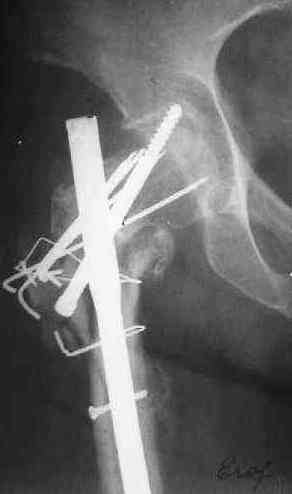

Поступила женщина 62 лет. В X 2006 оперировна в одной из горбольниц, по поводу, видимо, оскольчатого подвертельного перелома.

Почему сделан такой странный остеосинтез - пока неизвевстно. 3 мес. в тазобедренной гипсовой повязке. Картина через полгода после операци, в апреле - первый снимок. После этого снимка убрали винт, проникающий в сустав. Картина на сегодня - следующие 2 снимка.

Dear All,A female 62 y.o. referred to our unit. In X 2006 was operated somewhere - open reduction and fixation of a fragmented subtrochanteric fracture. Why so strange fixation was performed - no data at the moment. 3 month in plaster cast. Image 1 - Apr 2007, 6 month after the surgery. The screw was removed some days later.

Other images present the current situation.